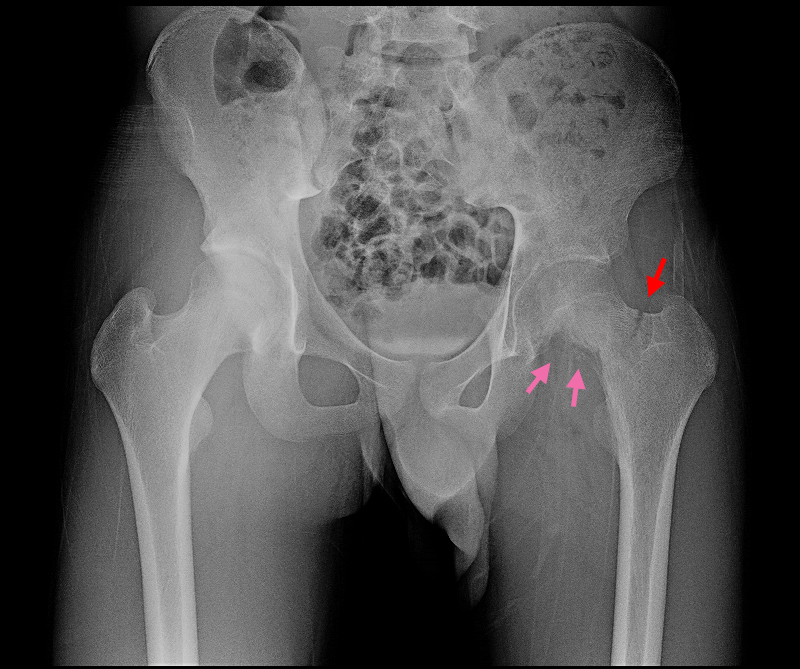

16才男 Xp1.jpg

MRI検査後のレントゲン像でも、大腿骨の骨頭部の下半分は溶けており(ピンク矢印)、外側よりは一部骨折している所見でした(赤矢印)。私は“骨肉腫”と判断し、骨腫瘍の専門家にその日のうちに紹介し、診察してもらいました。しかし、返信には「良性腫瘍の可能性が高い」という内容で、驚愕しました。